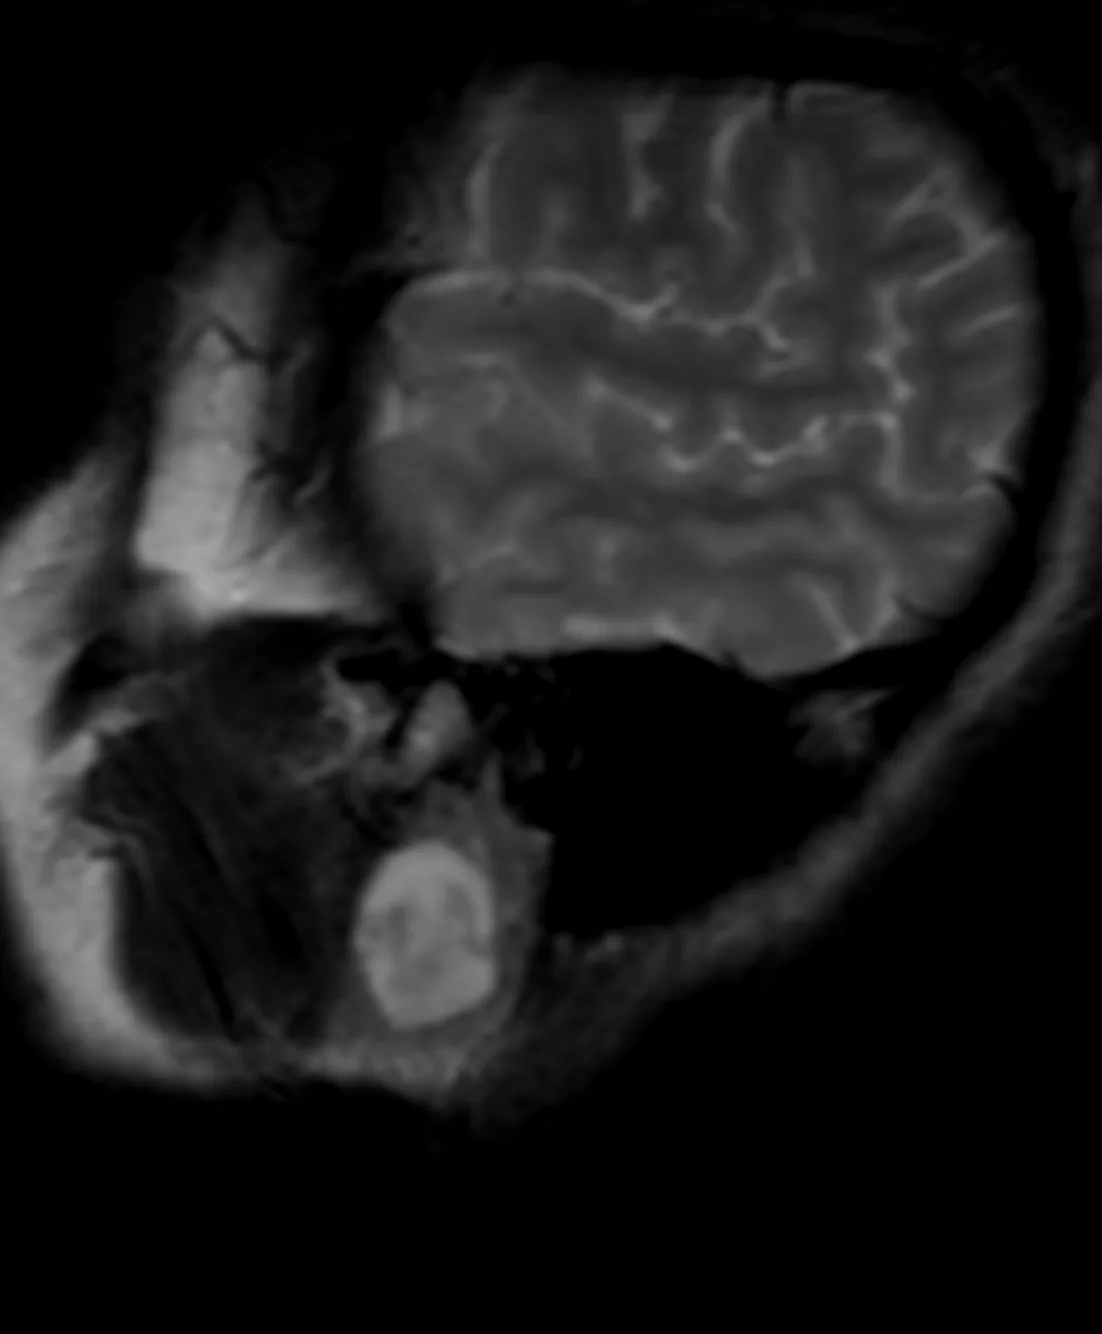

Клинический случай кавернозной мальформации, ассоциированной с венозной аномалией развития (ВАР). Следует напомнить, что ВАР часто сочетаются с каверномами, однако точные статистические данные не привожу, чтобы простимулировать самостоятельный поиск информации и закрепление знаний. Клиническая симптоматика у данного пациента отсутствует, что является типичным сценарием для подобных находок. Диагноз установлен случайно.